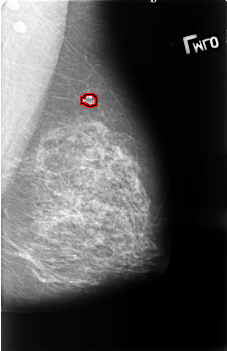

FILE: B_3406_1.LEFT_CC.OVERLAY

TOTAL_ABNORMALITIES 1

ABNORMALITY 1

LESION_TYPE CALCIFICATION TYPE COARSE DISTRIBUTION N/A

LESION_TYPE MASS SHAPE OVAL MARGINS CIRCUMSCRIBED

ASSESSMENT 2

SUBTLETY 3

PATHOLOGY BENIGN_WITHOUT_CALLBACK

TOTAL_OUTLINES 1